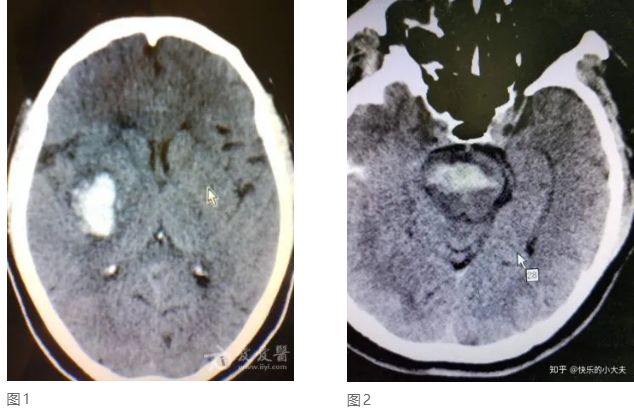

高血压脑出血,顾名思义,由于高血压造成的脑出血,其实高血压脑出血不是一日之功,首先人的脑血管随着年龄会发生粥样硬化,尤其当合并高血压、糖尿病、高脂血症、吸烟等危险因素时,加上人的脑血管较全身其它血管管壁要薄,由于情绪、天气、便秘、屏气等动作导致血压突升,从而引发硬化的血管发生破裂。最常见的破裂血管是起源于颅底大血管的穿通支,主要供应人的基底节、丘脑、桥脑等部位,因此,高血压脑出血最常见于基底节区(图1)、丘脑、桥脑(图2)等部位,也可见于小脑、大脑皮层、脑室等。由于出血部位深在,且位于人脑的重要功能区,因此高血压脑出血有着极高的致死率和致残率,而且手术效果不佳。所以,预防比治疗显得更为重要,随着高血压、糖尿病、高脂血症的逐渐低龄化,高血压脑出血也不再是老年人的专利,中青年的高血压脑出血也不算罕见了。如果发现高血压、高血脂及高血糖一定要及时治疗,防患于未然。